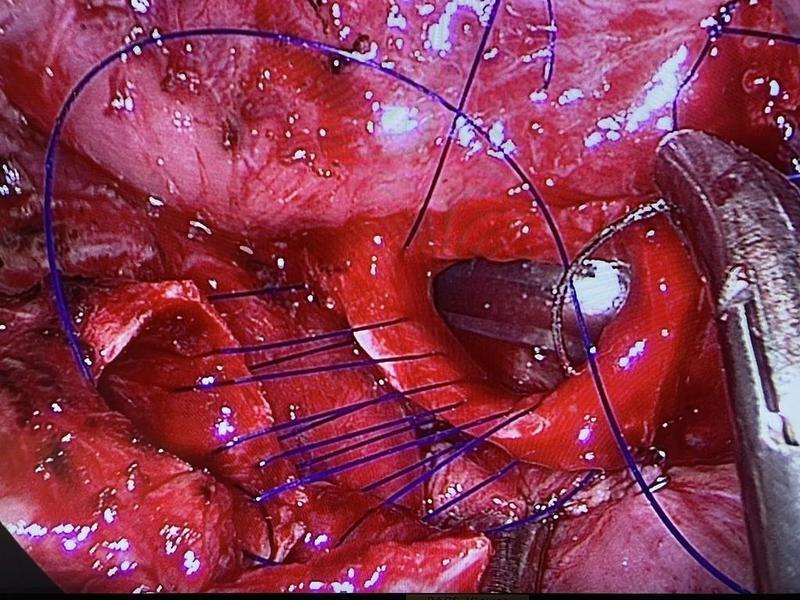

Con su técnica pionera llamada Uniportal VATS, consistente en abrir una incisión de no más de tres centímetros para poder introducir el instrumento médico que lleva una cámara incorporada para poder ver la operación en pantalla en tiempo real. De ahí que las siglas VATS se correspondan con Video Assisted Thoracic Surgery.

Es la primera vez en la historia que alguien realiza algo así. Ahora está esperando el próximo reto